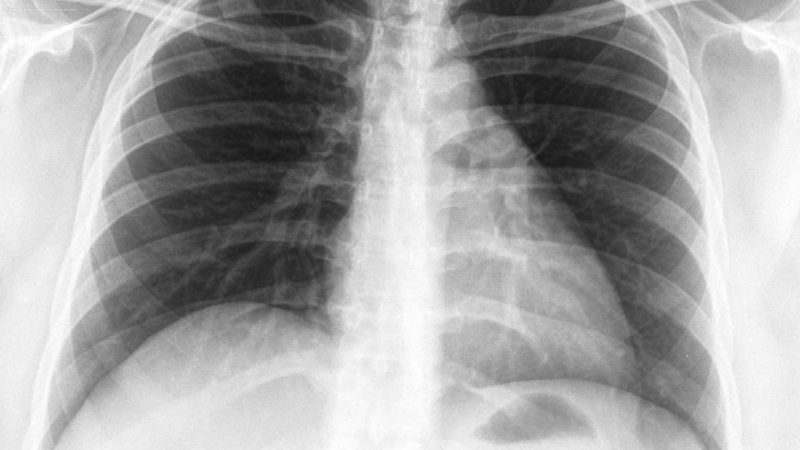

“Tuberculosis, also known as ‘batuk kering’, is an infectious disease caused by Mycobacterium tuberculosis and spreads through the air to those in close contact. Common symptoms include prolonged coughing, significant weight loss, loss of appetite, night sweats, and coughing up blood. TB is preventable and fully curable through effective treatment, which requires a minimum duration of six months,” the statement added.